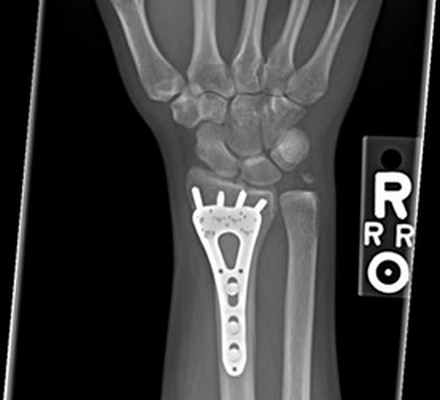

Перелом лучевой кости «в типичном месте» — перелом лучевой кости на 2–3 см проксимальнее суставной поверхности • Частота. 15–20% всех переломов. У пожилых женщин возникает в 2–3 раза чаще, чем у мужчин • Причины: падение на вытянутую руку с согнутой кистью • Патоморфология •• При падении на кисть в положении разгибания возникает разгибательный перелом Коллиса — дистальный отломок смещается в тыльную и лучевую сторону и супинирует, центральный смещается в ладонно-локтевую сторону •• При падении на кисть в положении ладонного сгибания возникает сгибательный перелом Смита — дистальный отломок смещается в ладонную сторону и пронирует, центральный — в тыльную сторону и супинирует • Клиническая картина: вилкообразная или штыкообразная деформация, при переломе Коллиса пальпируется на тыльной поверхности дистальный отломок, на ладонной — проксимальный, при переломе Смита дистальный отломок пальпируется на ладонной поверхности, проксимальный — на тыльной; резкая болезненность при пальпации лучевой кости и шиловидного отростка, осевой нагрузке. Часто повреждаются срединный нерв, межкостные ветви срединного и лучевого нервов (неврит Турнера) — резкие боли, парестезии, зоны анестезии, остеопороз костей кисти, ограничение движения IV пальца • Лечение •• Перелом без смещения — гипсовая лонгета (предплечье в среднем положении между супинацией и пронацией, кисть — лёгкое тыльное сгибание) на 3–4 нед •• Переломы со смещением — ручная или аппаратная репозиция, гипсовая повязка на 4–5 нед •• Неврит Турнера — витамины группы В, неостигмина метилсульфат, анаболические гормоны, тиреокальцитонин, прокаин внутрикостно.

Остеосинтез лучевой/локтевой кости пластиной

После выставления отломков в правильное положение металлическая пластина фиксируется на кости с помощью специальных винтов, не давая отломкам сместиться. Если сломаны и лучевая, и локтевая кость, устанавливается две пластины. После операции на руку накладывается защитная гипсовая лонгета, в среднем – на 2-3 недели. Средний срок госпитализации при подобном оперативном вмешательстве – 7 дней. После выписки необходимо делать перевязки в амбулаторном режиме (в поликлинике). Через 2-3 недели лонгета снимается, и назначается курс восстановительного лечения – лечебная физкультура, физиотерапия. Пластины удаляются в среднем через год.